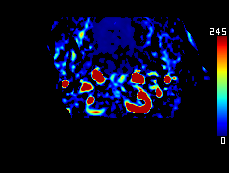

MRA collateral map: ‘DeepClue-Precise MR 측부혈류영상'

MR 혈관영상을 이용한 측부혈류영상

동맥기

모세혈관기

조기정맥기

후기정맥기

지연기

조기정맥기까지 남은 허혈 영역 : 초기 뇌경색 영역과 일치 (일치율 0.97)

모세혈관기의 허혈 영역 : 허혈반음영을 반영 (일치율 0.89)